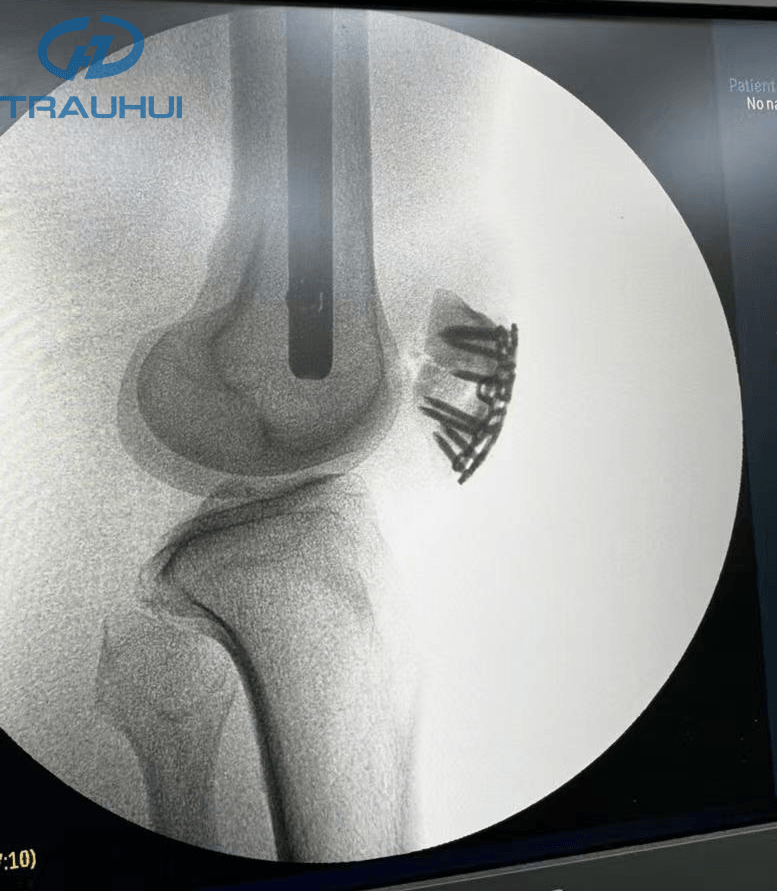

Anterior Patella Plates.jpg

Figure 1: Cottey MD Variable Angle Locking Plate System-Anterior Patella Plates

Anterior Patella Plates1.png

Figure 2: X-Ray